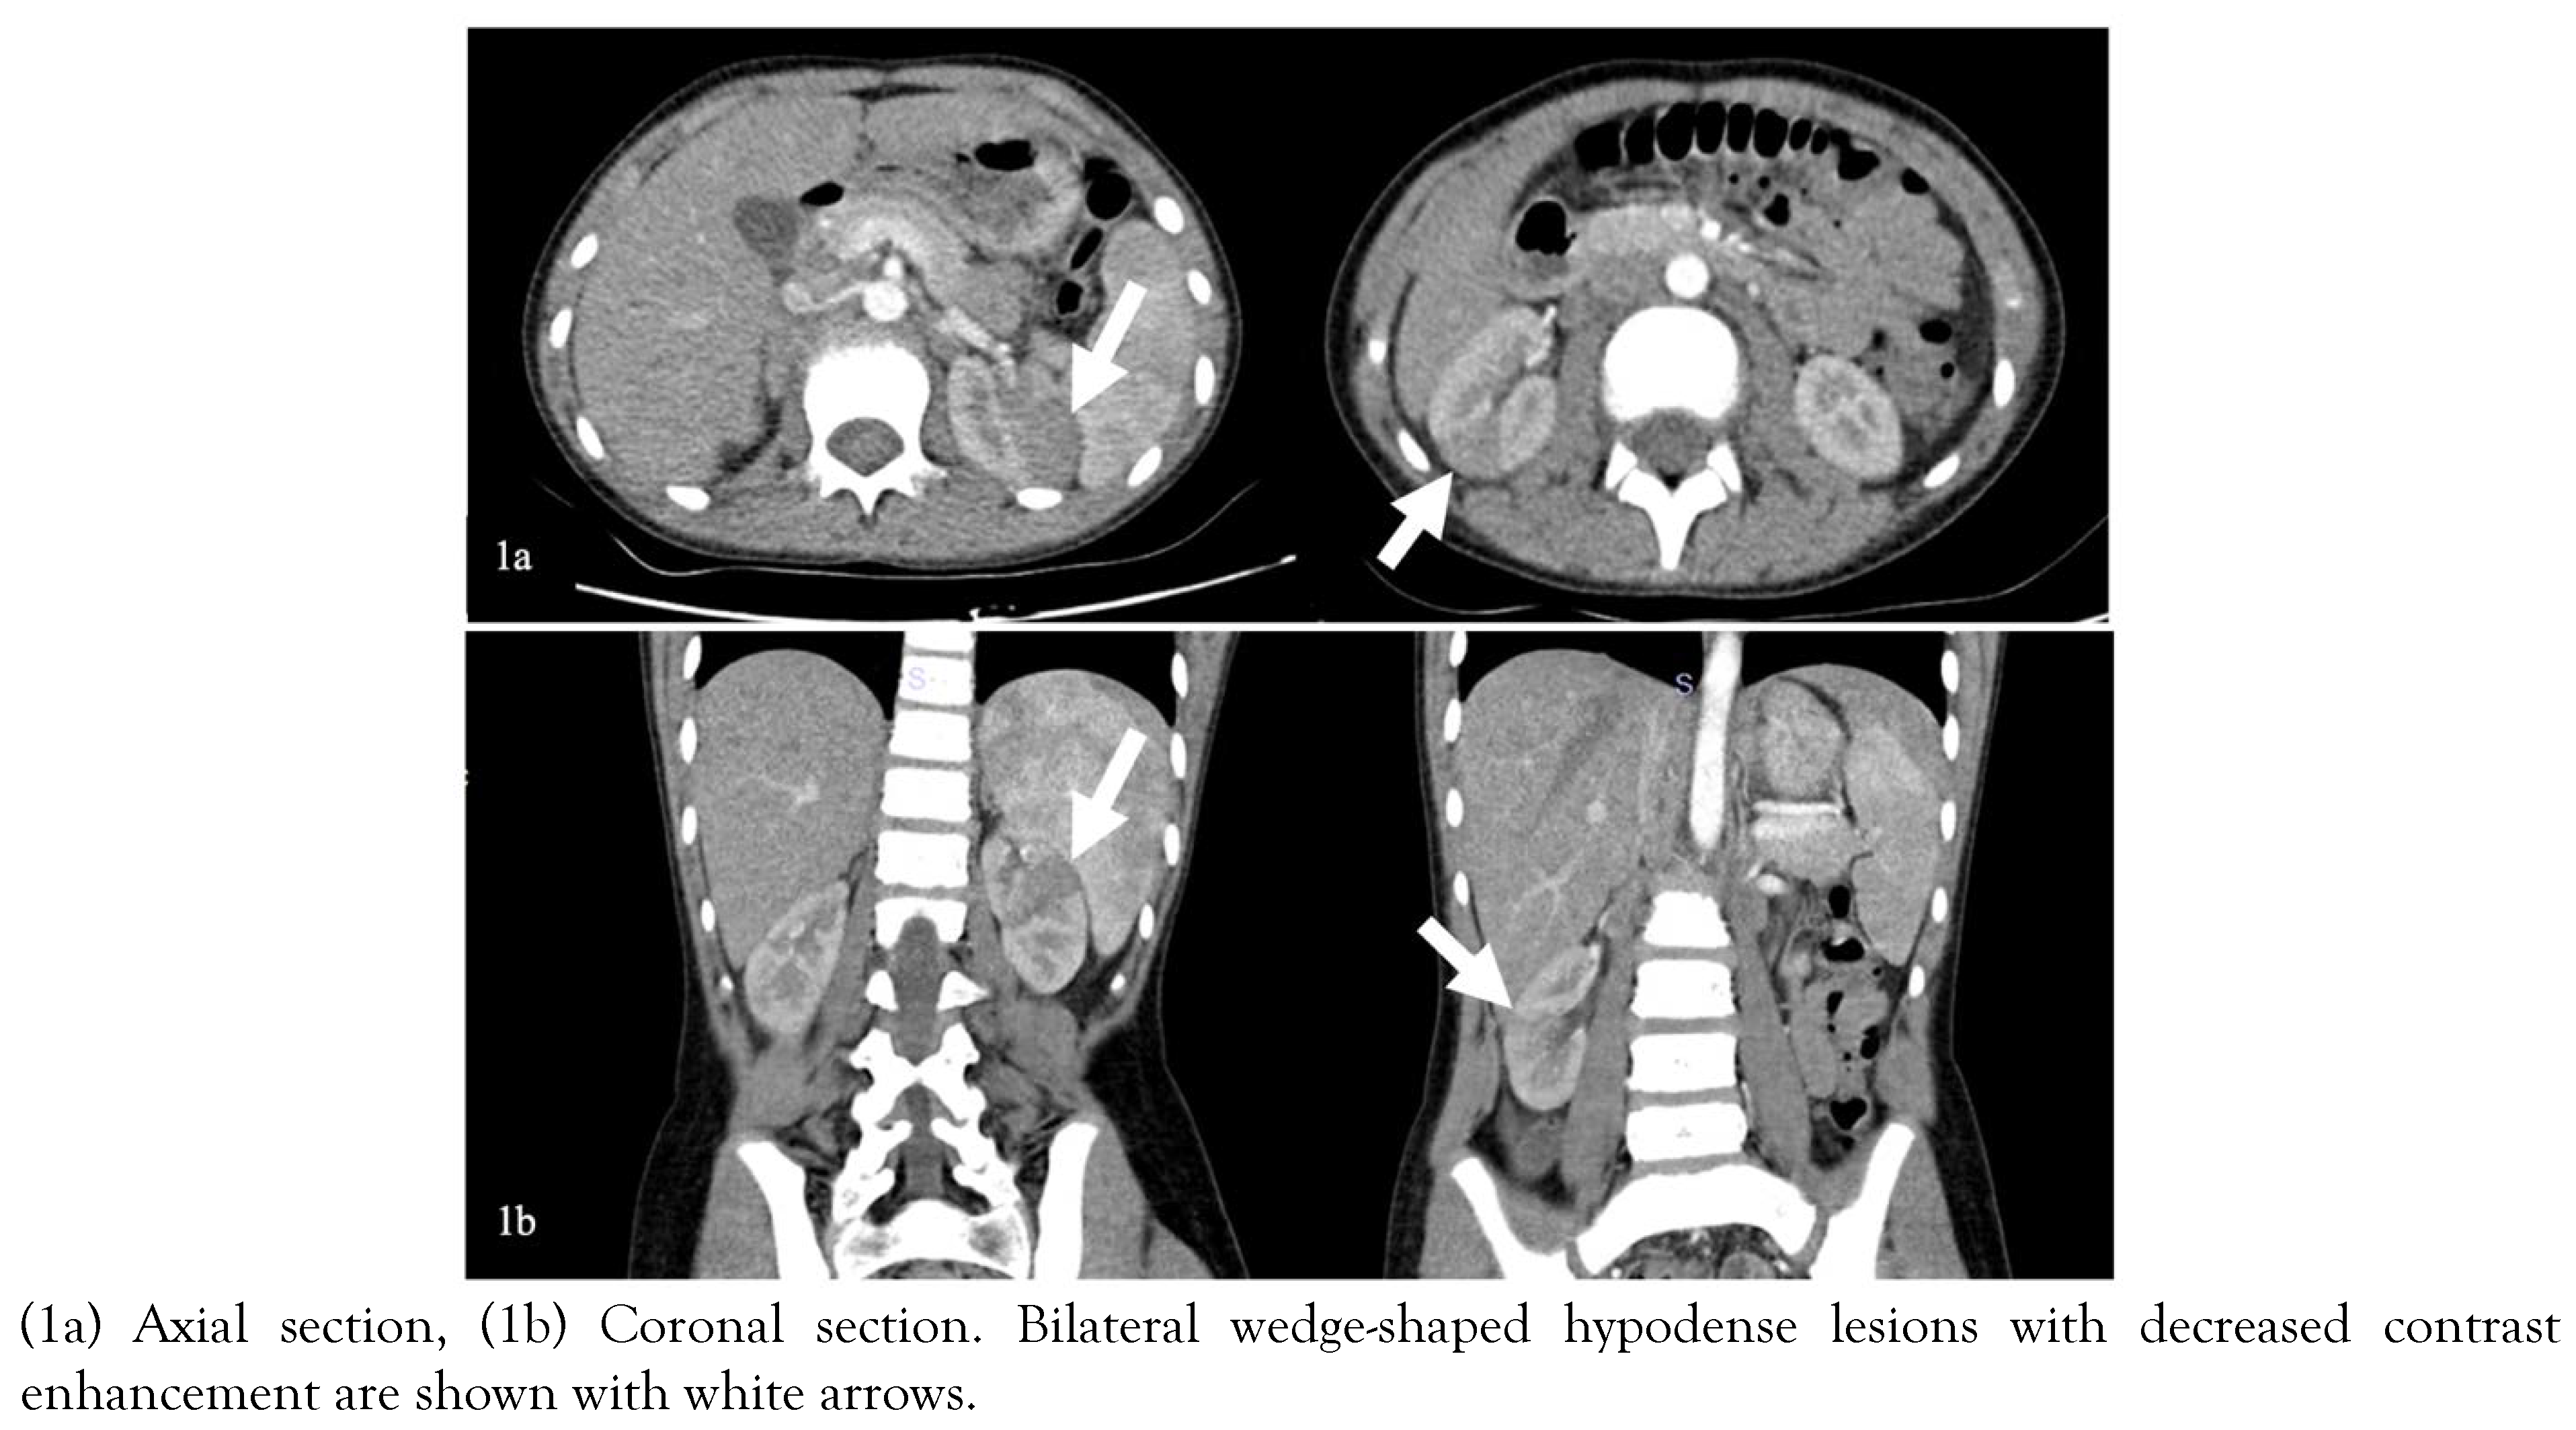

Clinical course of both cases

Due to the acute abdomen clinical finding in Case-2 and the significant CVA tenderness in both cases (bilateral in Case-1 and unilateral in Case-2), contrast-enhanced abdominal computed tomography (CT) was performed for differential diagnosis. In Case-1, nonhomogeneous hypodense mass-like lesions with decreased contrast enhancement in both kidneys were detected (Figure 1). In Case-2, a similar lesion was seen in the lower pole of the right kidney (Figure 2). Both cases were diagnosed with AFBN since these lesions were specific for it.

Costovertebral angle tenderness is one of the specific indicators for kidney pathology and is often seen in acute pyelonephritis [12]. However, it may present in other diseases such as nephrolithiasis, kidney abscess, vesicoureteral reflux, obstructive pathologies of the urinary tract, retrocecal appendicitis, retroperitoneal abscess [13]. In a patient presenting with fever and CVA tenderness, the clinician should consider first upper UTI, among other diagnoses. In selected cases, imaging techniques can be used for differential diagnosis. Herein, due to the presence of CVA tenderness, we performed contrast-enhanced CT imaging, which showed hypodense wedge-shaped kidney lesions indicating AFBN (Figure 1 and 2) [14].

Early diagnosis and effective treatment are essential in terms of preventing renal scars and morbidity such as hypertension, proteinuria, and renal failure [18]. The diagnosis of AFBN is based on radiologic examinations. In many cases, there is no finding on kidney ultrasonography (USG), although it may show nephromegaly, focal lesions with poorly defined irregular margins. Contrast-enhanced abdomen CT is the gold standard imaging technique for the diagnosis of AFBN. Herein, both cases had no finding on kidney USG. The lesions were observed on CT as the typical wedge-shaped, poorly defined hypodense lesions after contrast-medium administration [14]. The DMSA scan of the kidneys may help in the diagnosis of AFBN and the detection of renal scarring during follow-up [19]. In Case-1, the diagnosis of AFBN was supported with the DMSA scan. In Case-2, the DMSA scan in follow-up shows no scars indicating the effective treatment.

Figure 1. Images of contrast-enhanced abdominal CT of Case-1.